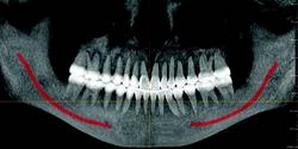

CBCT devices may be used for traditional forms of radiography, in addition to advanced 3-D volumetric renderings. Conventional cephalometric measurements may be obtained through 3-D volumetric images by rendering the image as a 2-D projection resembling a radiograph or a panoramic image. It is also possible to digitize cephalometric points in 3-D, resulting in the introduction of multiple analyses.

Non-conventional renderings are also realized using CT data. In fact, X-ray projections that are non-physical are possible. For example, a cephalogram can be created where the patient’s neck vertebrae have been omitted. The advantage of this type of rendering is that in a conventional ceph, the vertebrae may obfuscate the dentition, whereas in a non-conventional rendering, they do not.